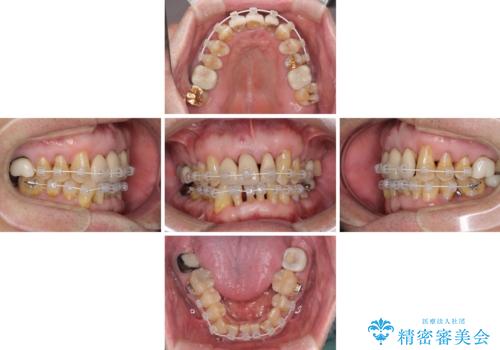

また、前歯の部分矯正も希望されたため、歯周外科処置と平行して矯正治療を行うこととしました。

患者様ご自身が痛みには強いとおっしゃっていたので、治療中は特に辛いと感じることはなく進めることができました。